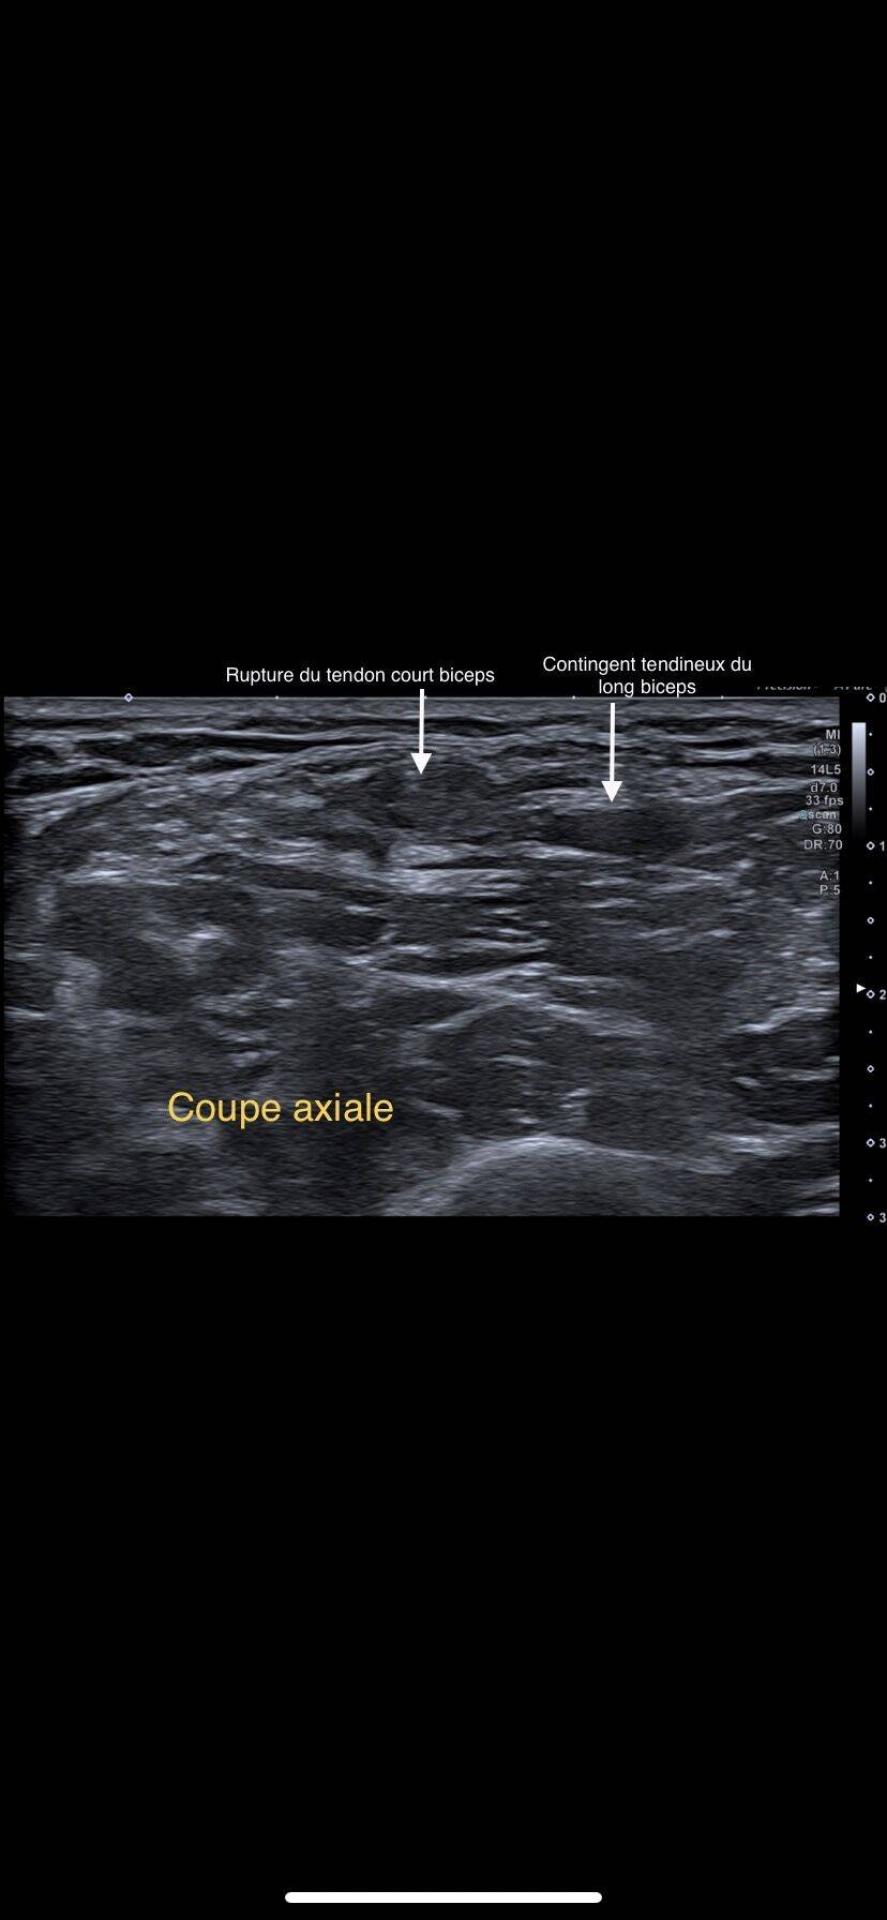

Patient venu consulter pour une perte de force en flexion contrarié de l’avant bras avec apparition d’une dépression du galbe au tiers inférieur du bras, sans signe de Popeye associé.L’échographie des muscles et des tendons du bras confirme une interruption des fibres  tendineuses du court biceps ...